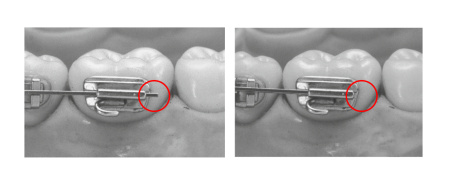

Инструкция по стерилизации TASK